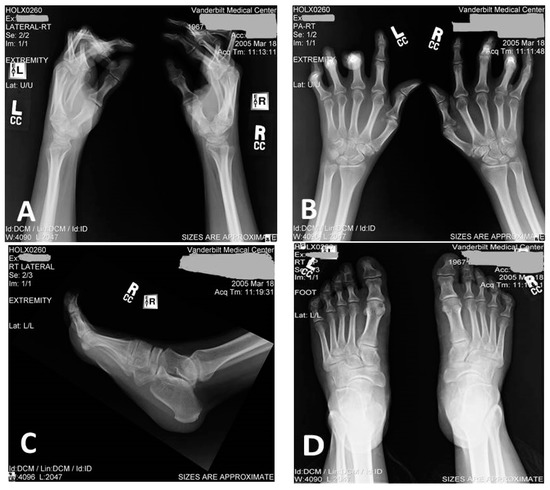

| I/2 | Both hands and feet with bilateral pes equinovarus | Yes, with wheelchair-dependency in her 50s | 30s | Unknown |

| II/1 | Mild hand deformities | Yes, required an assistive device in her 50s and wheelchair in her 60s | 30 | Yes (history of passing very dark urine) |

| II/2 | Severe hand deformities, mild feet deformities | Yes, required assistive device in his 60s, wheelchair in his 70s | 39 | Yes (history of passing very dark urine) |

| III/1 | Mild hand deformities | Yes, abnormal but independent gait at age 47 years | 27 | Yes (documented elevation of CPK and myoglobinuria) |

| III/2 | Severe hand deformities, mild feet deformities | Yes, abnormal but independent gait at age of 51 years | 32 | Yes (documented elevation of CPK and myoglobinuria) |